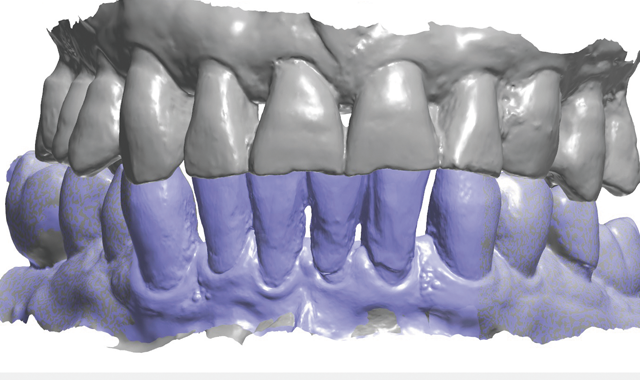

Fig. 4

Treatment began by taking an intraoral 3D impression scan (3Shape TRIOS 3) (Fig. 4), after which a digital diagnostic “waxup” was created using Dental Designer (Fig. 5). Using digital intraoral scanning and digital “waxups” eliminated the need for time-consuming conventional impression taking, saving the patient time and eliminating discomfort. Additionally, proper shading, tooth size and contouring could be determined by examining and manipulating the digital impression/model images and

Fig. 5

discussing the proposed changes with the patient.